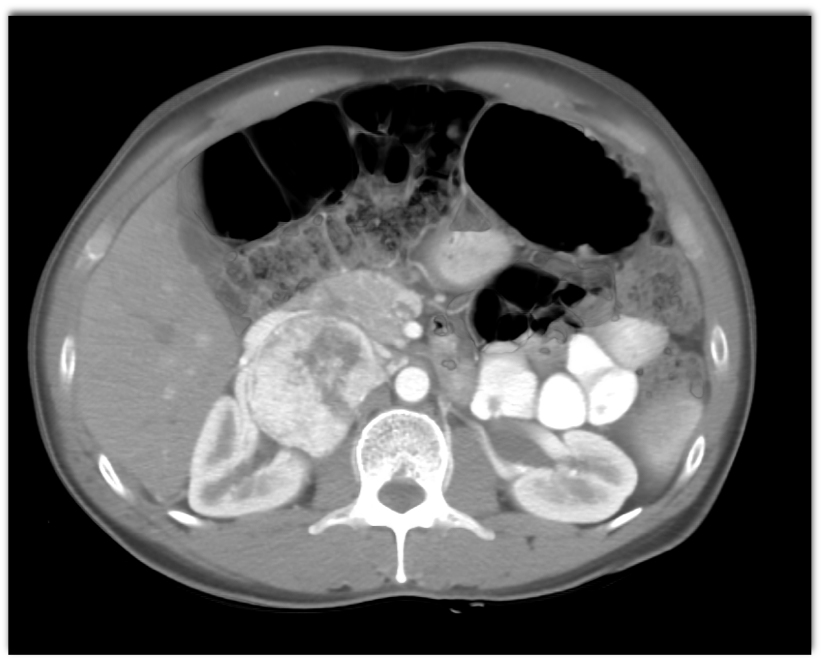

6) The most likely diagnosis in this case is

clear cell renal cell carcinoma

renal lymphoma

papillary renal cell carcinoma

chromophobe adenoma